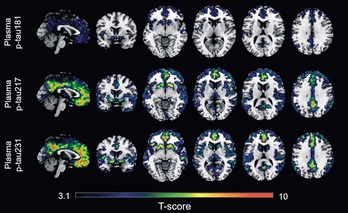

Un estudio detecta dos biomarcadores en sangre que captan los primeros indicios del alzhéimer NAIZ 2022.08.11